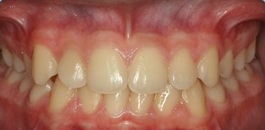

Documentação ortodôntica digital

Documentação composta de radiografias, fotografias, modelos e análises cefalométricas com o objetivo de realizar um estudo detalhada da interrelação das estruturas dento faciais do paciente. Possibilitando a escolha do tratamento correto para o mesmo. Indicação: Tratamentos Ortodônticos e Ortopédicos.